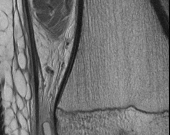

A 65-year-old male presents with classic symptoms of neurogenic claudication. He reports bilateral leg pain and fatigue that worsens with walking but is reliably relieved by leaning forward onto a shopping cart. In the pathogenesis of degenerative lumbar spinal stenosis, which structure is primarily responsible for dynamic central canal compression during spinal extension?

Explanation

In degenerative lumbar spinal stenosis, extension of the spine decreases the sagittal diameter of the canal because the ligamentum flavum buckles inward (shingling), dynamically compressing the thecal sac. Flexion of the spine pulls the ligamentum flavum taut, increasing the available canal space and alleviating neurogenic claudication symptoms. Hypertrophic ligamentum flavum is a major structural contributor to central stenosis.